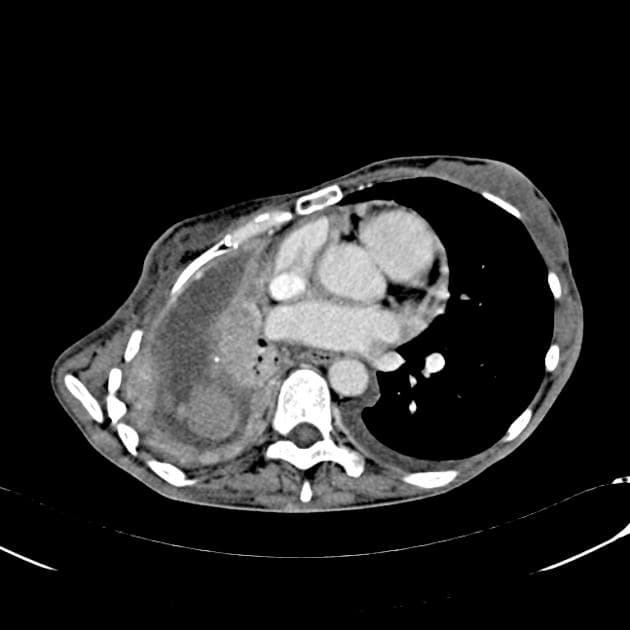

- Khối bất thường kích thước gần 9 cm ở tâm nhĩ phải, tăng quang không đồng nhất, gây hẹp đoạn nối giữa tĩnh mạch chủ trên và tâm nhĩ phải (superior cavoatrial junction).

- Khối xâm lấn màng ngoài tim với hình ảnh dày lên dạng nốt (nodular pericardial thickening) và vệt tăng tỷ trọng ở mỡ màng ngoài tim (pericardial fat stranding).

- Hơn 20 nốt nhỏ ở mỗi phổi, kích thước tối đa 6 mm, nhiều nốt có vùng mờ kính (ground-glass attenuation) xung quanh, gợi ý bệnh lý di căn xuất huyết (hemorrhagic metastatic disease).

- Tràn dịch màng phổi (pleural effusion) hai bên, lượng ít.

Hình ảnh điển hình của u ác tính mạch máu tim (angiosarcoma): các khối u ác tính nguyên phát tại tim thường gặp ở tâm nhĩ phải và xâm lấn màng ngoài tim. Các nốt phổi cho thấy bệnh lý di căn đến phổi (metastatic disease to lung).

- "Đặc điểm hình ảnh bao gồm khối xâm lấn ở tâm nhĩ phải, xâm lấn màng ngoài tim và thường có di căn theo đường máu, đặc biệt đến phổi."